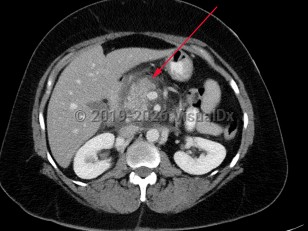

Chest pain, Pleural effusion, 50-59 year old Female

Spontaneous rupture of esophagus

Acute pancreatitis